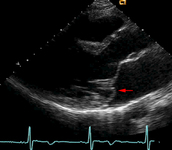

Prolapso da valva mitral

Ecocardiograma do eixo paraesternal longitudinal da valva mitral ilustrando prolapso do folheto posterior (seta vermelha)

Do acervo pessoal do Dr. Brian Griffin, MD; usado com permissão